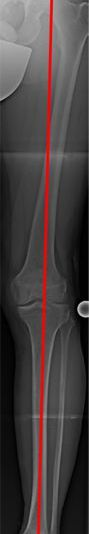

Die Linie, die Hüftkopfmitte und Sprunggelenksmitte verbindet, ist die mechanische Achse (MA) eines Beines (Bild 1a). Durch die MA wird das Knie in ein inneres (medialen) und äußeres (medialen) Kompartiment geteilt.

Sie verläuft im Normalfall durch die Mitte (Zentrum) des Kniegelenkes und führt dort zu einer Lastverteilung, die zu 75% die Innenseite und zu 25% die Außeneite des Gelenkes trifft.

Dies ist die „normale“ Lastverteilung zwischen dem inneren und äußeren Kompartiment des Knies.

Abweichender Verlauf der MA, links innenseitig (O-Bein), rechts außenseitig (X-Bein) und die dadurch entstehende Überbelastung (Bild 1b).